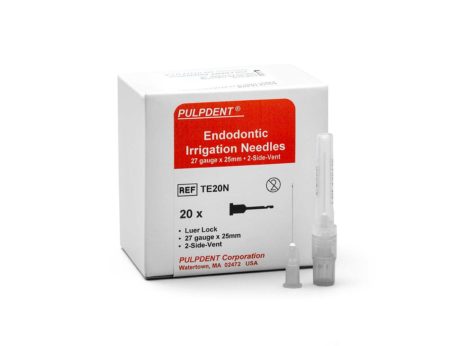

TE20N – TempCanal™ Enhanced endodontic irrigation needles, (27-gauge x 1”, 2-side-vent) Pkg. of 20